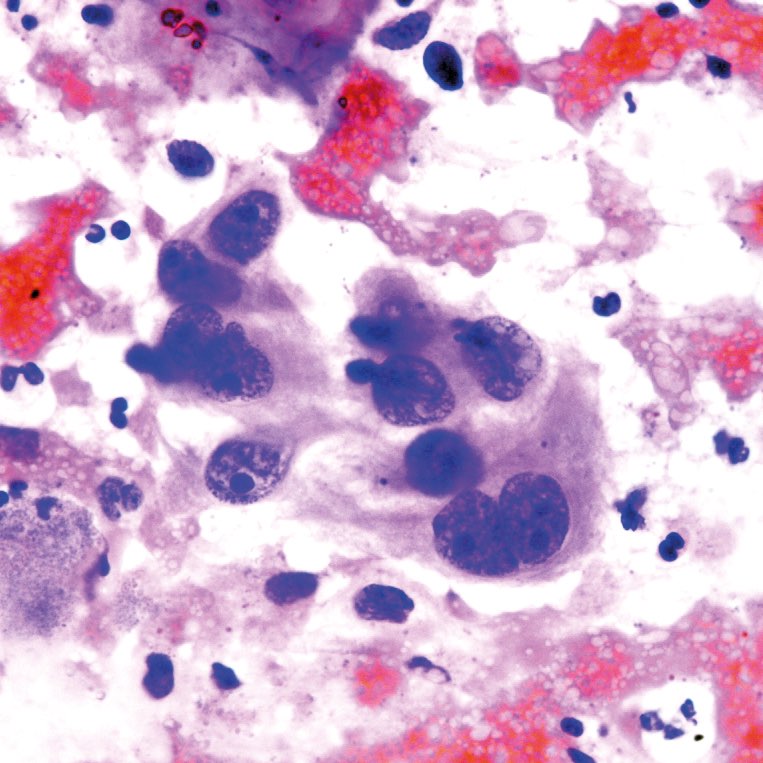

Abb. 1 - 4: Ausstrich von Milchröpfchen; H&E, A-C: origin. Obj. 40x,

Abb. 4: zusätzlich etwas vergrößert

Viele Makrophagen, darunter auch eine mehrkernige, mit fein-granulärem bis fein-vakuolärem Zytoplasma (Abb. 1-4). In Abb. 4 eine Gruppe von Epithelien mit uneinheitlich geformten hyperchromatischen Kernen und mehr grob-vakuolärem Zytoplasma. Der Ausstrichhintergrund enthält massenhaft bläschenartige Lipidtröpfchen.

Als Galaktorrhoe bezeichnet man Milchfluss außerhalb der Schwangerschaft und Stillperiode. Ursache ist eine erhöhte Prolaktinbildung in der Hypophyse. Sie kann durch einen Tumor von Hypophyse und Hypothalamus, aber auch durch verschiedene Medikamente (Antidepressiva, Antihypertonika, Antikoagulantien) und sogar durch ein Thoraxtrauma ausgelöst werden. Die Masse bläschenartiger Gebilde im Ausstrichhintergrund entsprechen durch die Alkoholfixation aufgelösten Lipidtröpfchen, die feinen Granula im Zytoplasma der Makrophagen Eiweißpartikeln der Milch. Beides, insbesondere die bläschenförmigen Gebilde, sind regelmäßig in der Stillphase nachweisbar. Die Epithelien in Abb. 4 sind wegen ihrer polymorphen Kerne besorgniserregend. Solche Zellen werden häufig auch in Feinnadelaspirationen von Brustveränderungen während der Laktationsphase gefunden und erfordern besonders bei Patientinnen im 4. Lebensjahrzehnt eine Ultraschalluntersuchung der Brust und klinische Kontrolle.